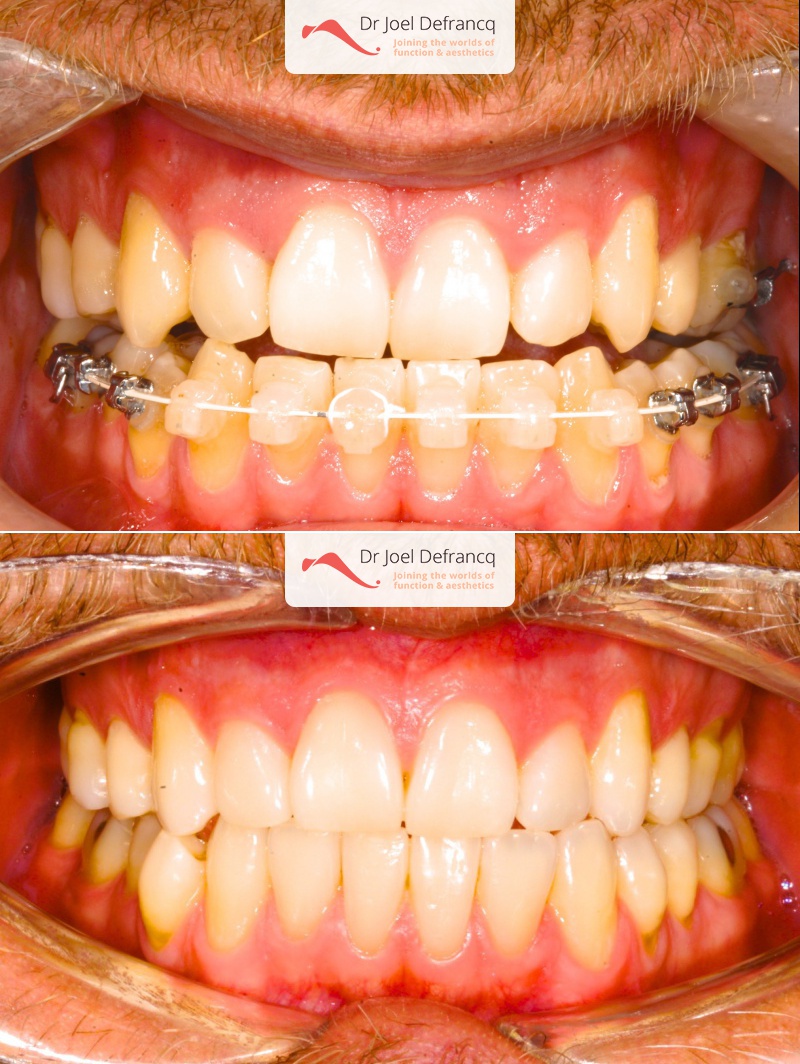

Natan: Kaakchirurgie voor en na. Te nauwe bovenkaak

Diagnose van het gezicht

- Te kleine bovenkaak

Dentale diagnose

- Klasse III

- Randbeet

Kaakchirurgie

- Verlenging bovenkaak (Le Fort I)

- Verbreden bovenkaak (Smile distractor)